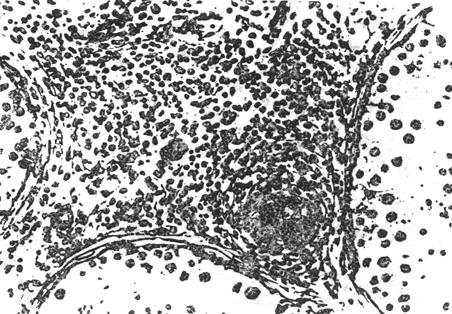

④唯支持细胞综合征:睾丸曲细精管内仅有支持细胞,间质细胞有明显增生,基底膜增原,无生精功能。此病变多系先天性异常。有少数继发睾丸功能严重受损的病例镜下可见曲细精管生精细胞几乎完全脱落,仅留下支持细胞,基底膜增厚且透明样变。

图8-3-6 唯支持细胞综合征,曲细精管内只有支持细胞